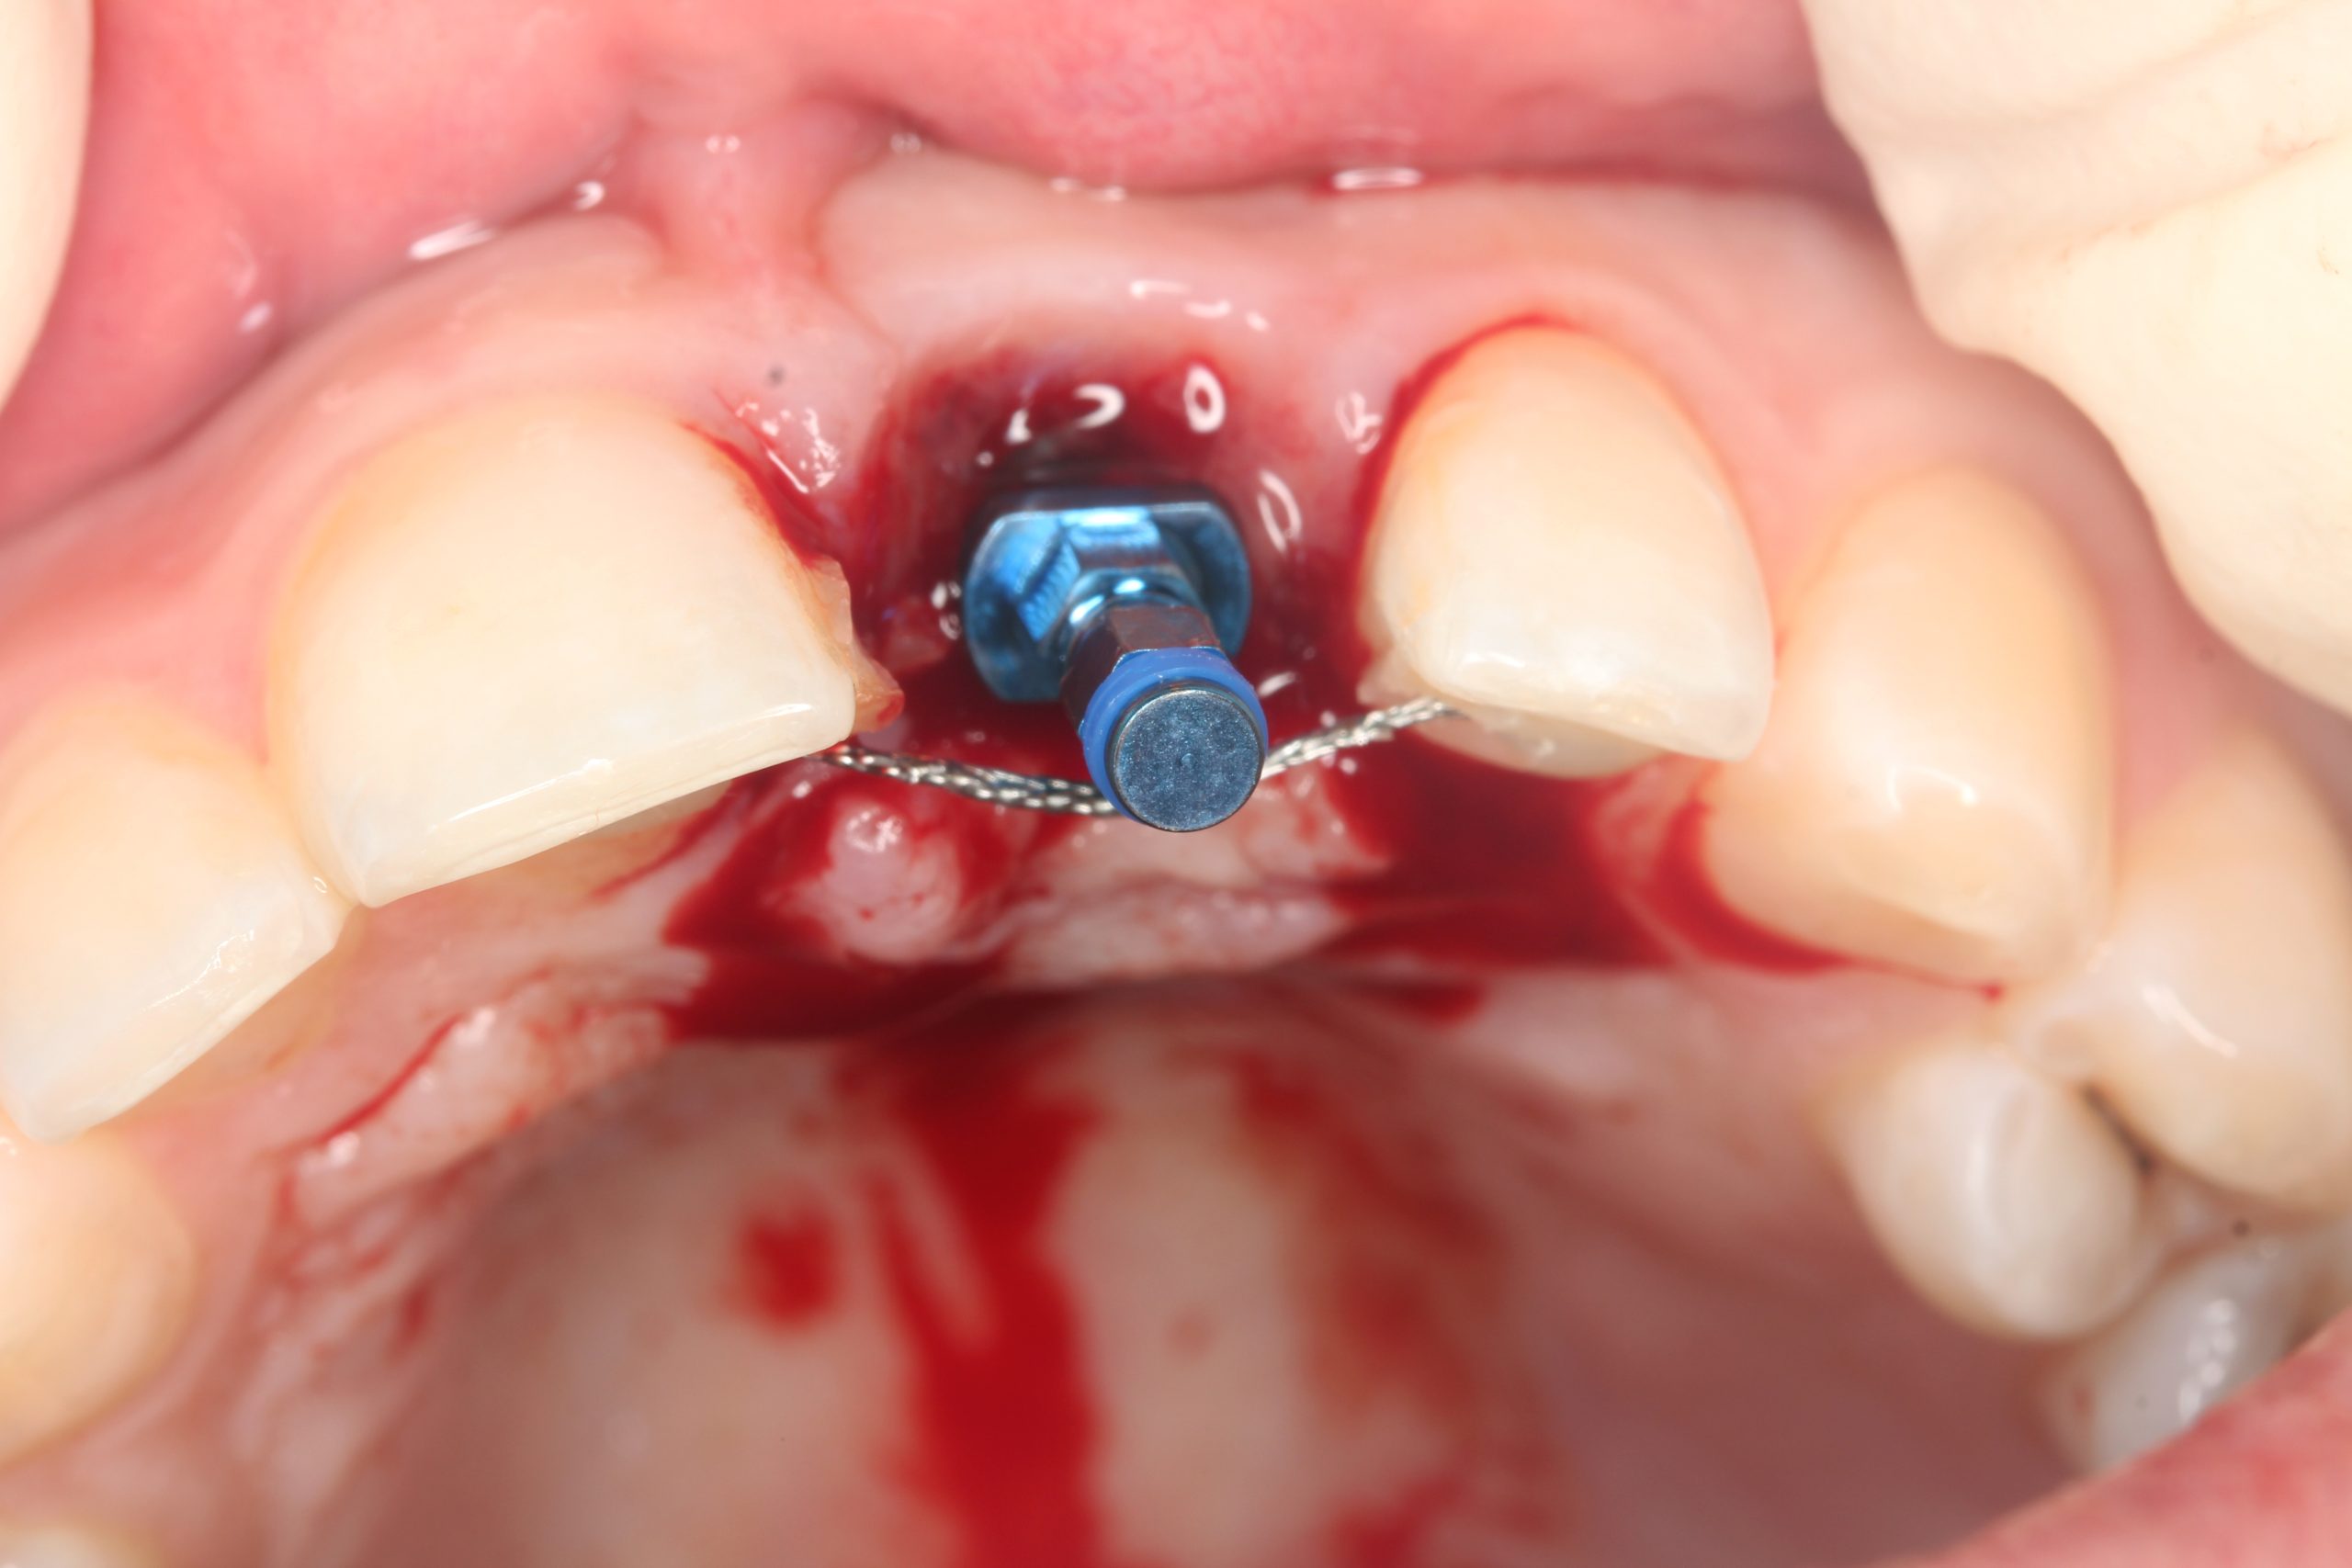

Nach dem Entfernen der Krone: eine perfekt epithelisierte Extraktionswunde und erhaltene Interdentalpapillen. Die Drahtschiene, mit der die Zahnkrone zeitweilig fixiert worden war, wurde als Kontrollelement für das Einsetzen des Implantats vorübergehend zurückbehalten.

Der Mukoperiostlappen wurde palatinal angehoben und teilweise vestibulär mobilisiert. Ein 14 mm langes Implantat BioniQ® von LASAK mit Ø 4 mm wurde eingesetzt und nach dem Entfernen des Trägers ein provisorischer Aufbaupfosten befestigt.